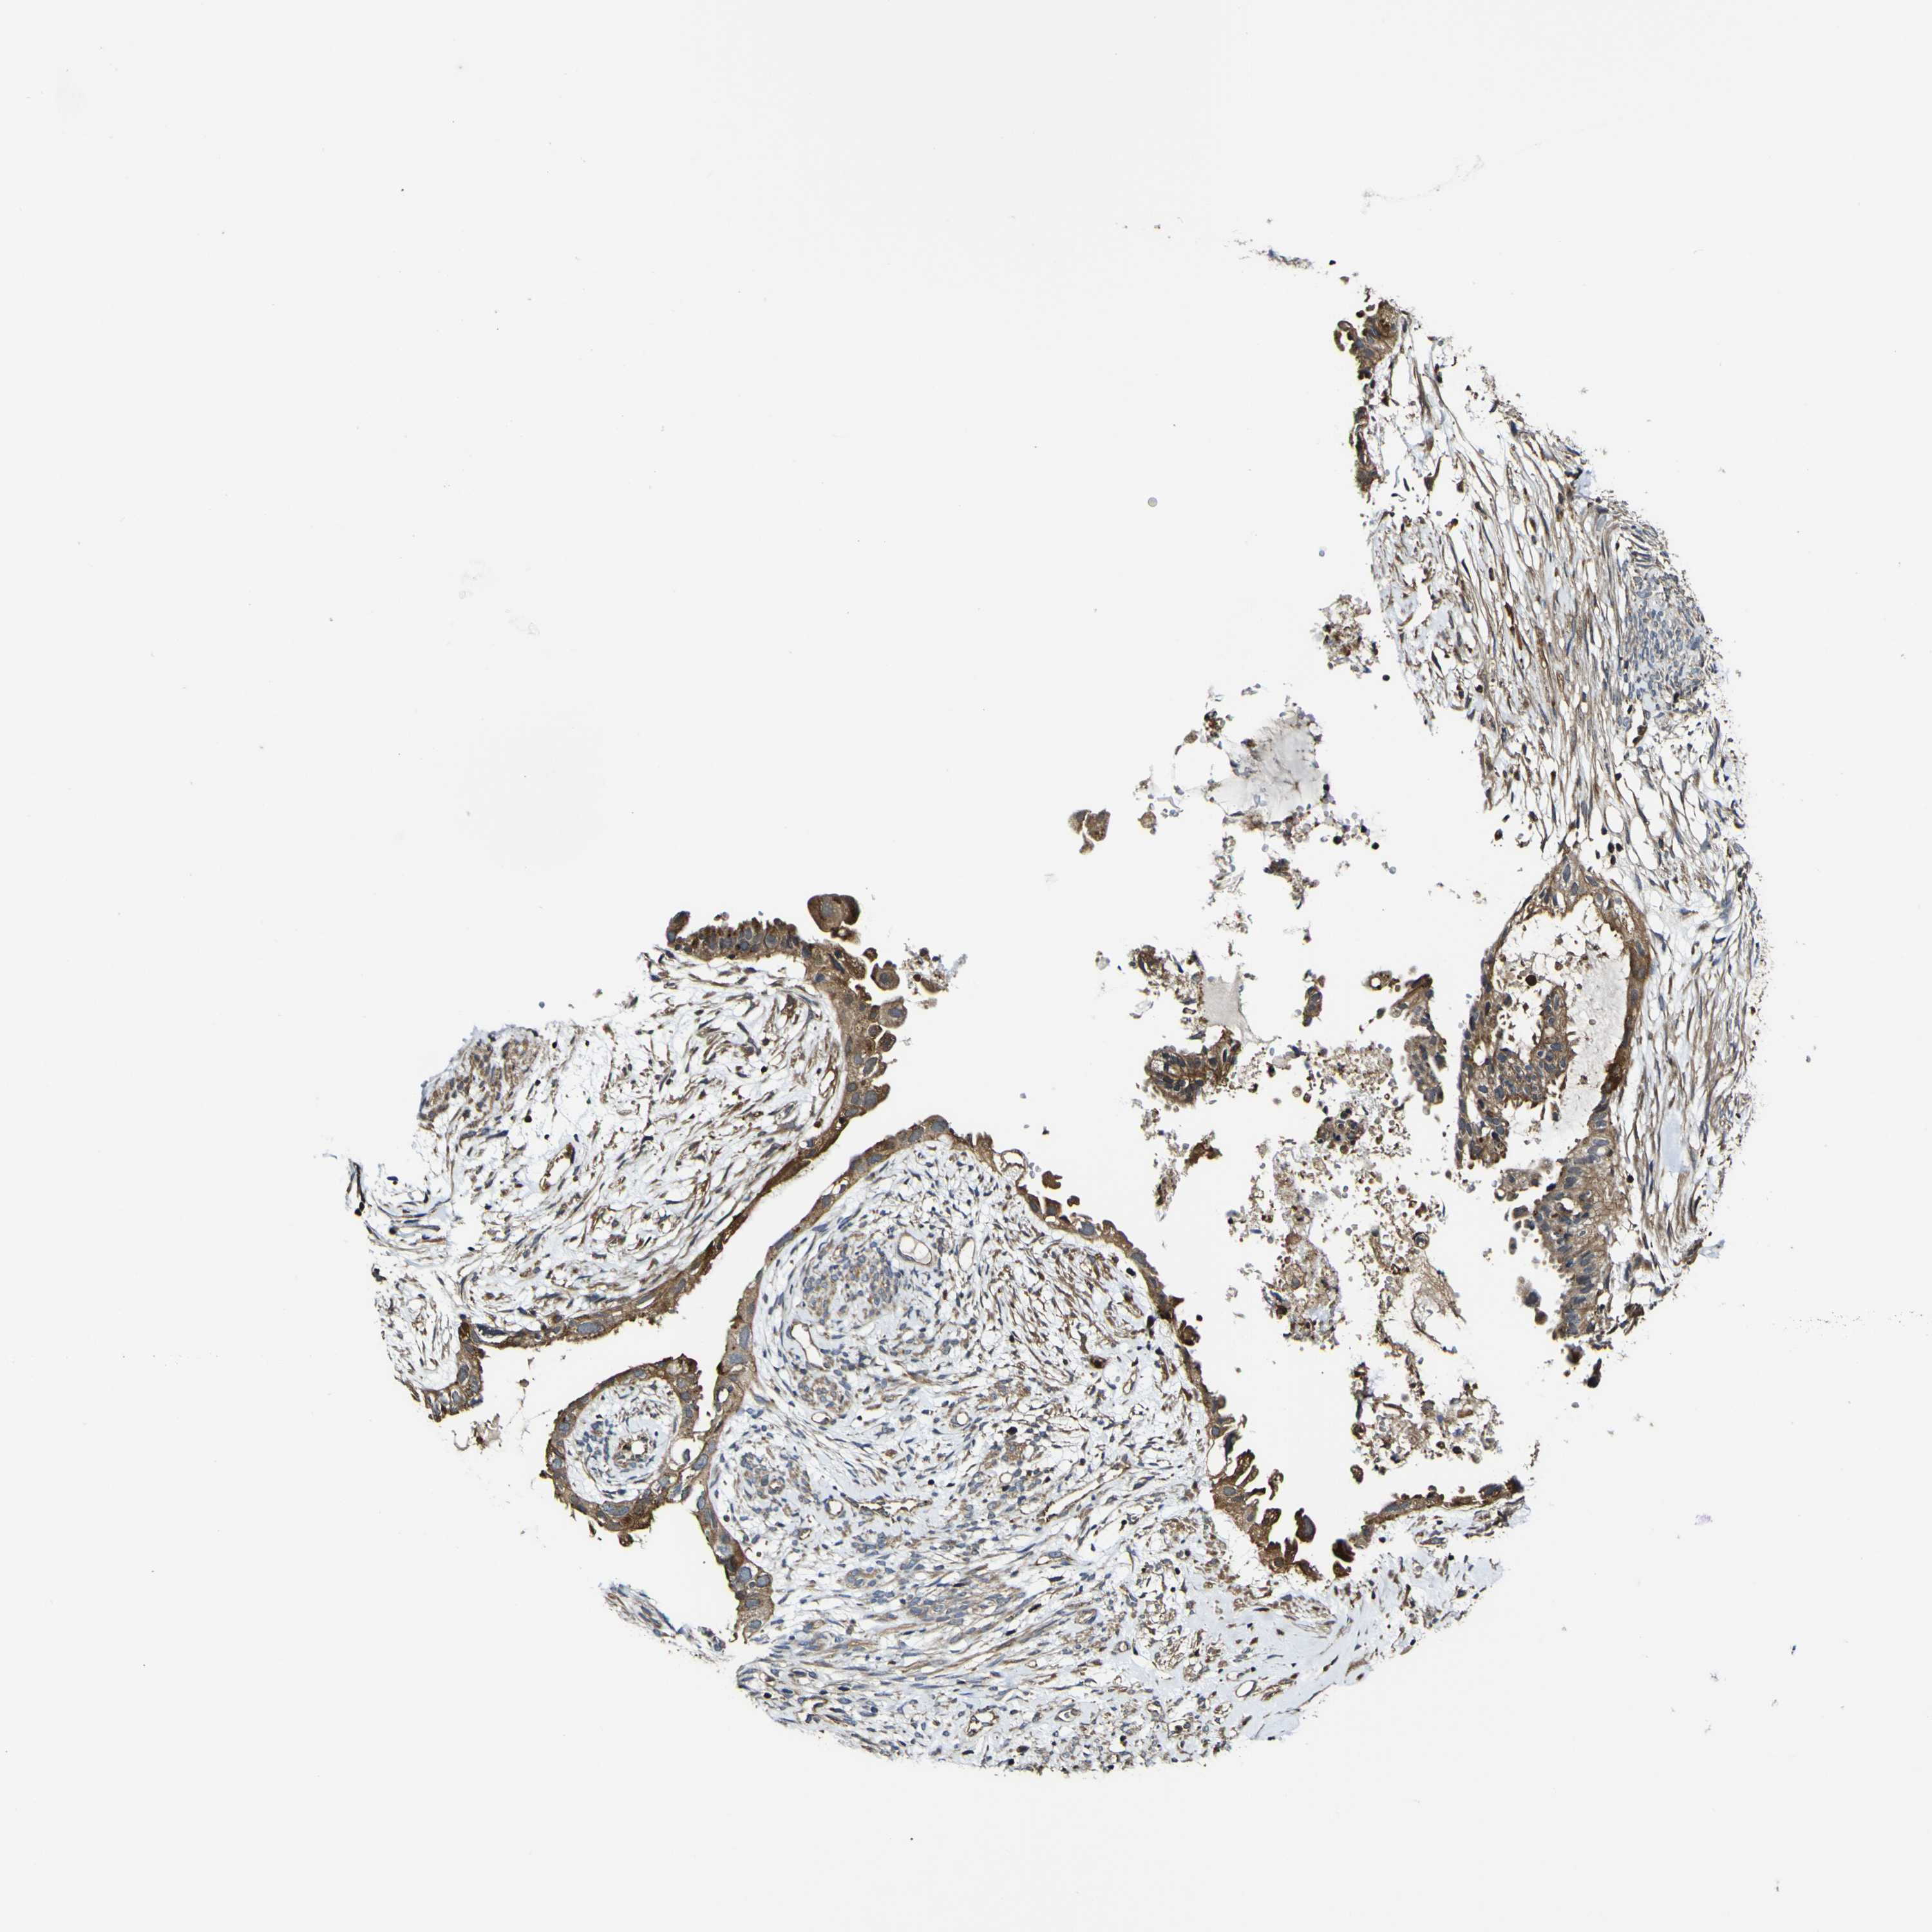

CERVICAL CANCER - Protein expressioni

A mouse-over function shows sample information and annotation data. Click on an image to view it in a full screen mode. Samples can be filtered based on level of antibody staining by selecting one or several of the following categories: high, medium, low and not detected. The assay and annotation is described here.

Note that samples used for immunohistochemistry by the Human Protein Atlas do not correspond to samples in the TCGA dataset.

Antibody stainingi

Antibody staining in the annotated cell types in the current human tissue is reported as not detected, low, medium, or high, based on conventional immunohistochemistry profiling in selected tissues. This score is based on the combination of the staining intensity and fraction of stained cells.

Each image is clickable and will lead to virtual microscopy that enables deeper exploration of all samples and also displays staining intensity scores, fraction scores and subcellular localization as well as patient and tissue information for each sample.

Antibody HPA012128

Antibody HPA012297

Staining

High

Medium

Low

Not detected

Intensity

Strong

Moderate

Weak

Negative

Quantity

>75%

75%-25%

<25%

None

Location

Nuclear

Cytoplasmic/membranous

Cytoplasmic/membranous,nuclear

Squamous cell carcinoma, NOS

Adenocarcinoma, NOS